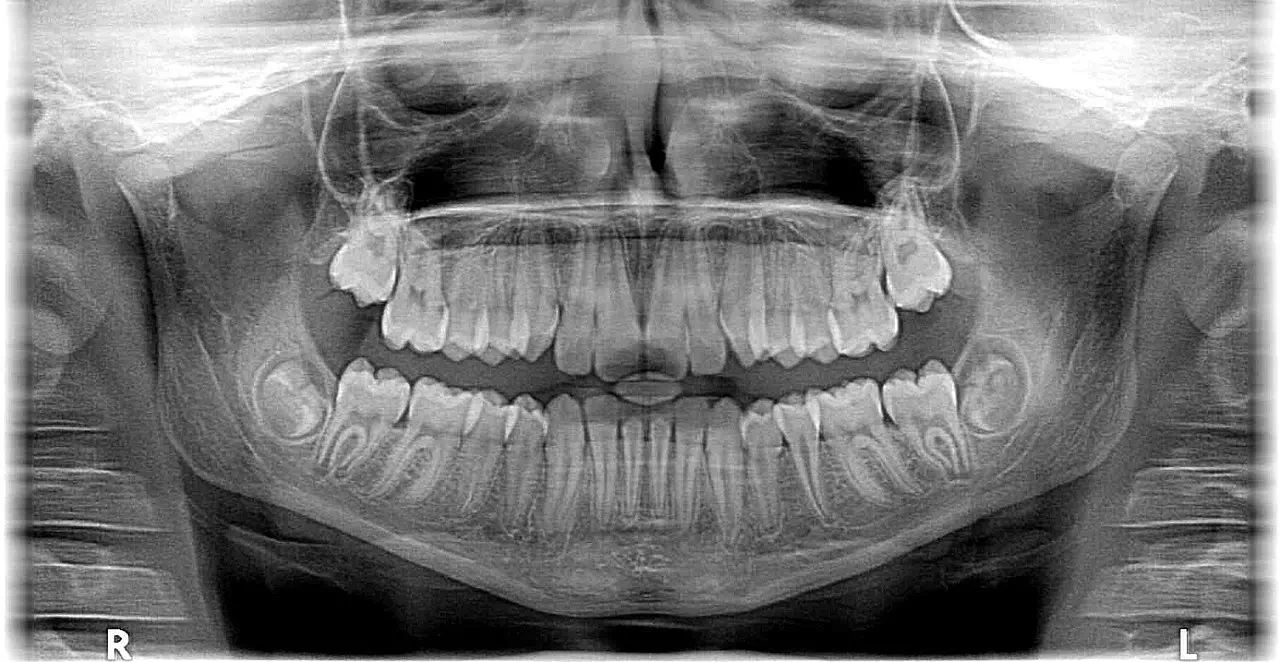

親知らずが痛む、歯科でレントゲンを撮影したら親知らずが埋まっていると指摘された、なかなか永久歯が萌出してこないなどの症状です。

埋伏歯は、歯が骨の中に埋まったままの状態を指します。特に親知らずは横向きに萌出していたり、神経の近くに位置していたりと、複雑なケースが多く見られます。放置すると痛みや腫脹、隣接する歯を損傷する原因となります。また、骨の中で炎症を起こすと顔面の腫脹や激しい痛みを伴うこともあります。

顎骨が膨隆してきた、歯科でレントゲンを撮影したら顎骨に透過像があると指摘されたなどの症状です。

顎嚢胞は顎骨内に液体が貯留した袋状の病変です。初期には自覚症状がほとんどありませんが、徐々に拡大し顎骨を膨隆させることがあります。放置すると骨を破壊したり神経を圧迫したりする可能性があるため、発見次第の治療が必要です。

精密な診断のため最新の設備を導入しています。3D CTスキャンはお口の中を立体的に撮影することで、通常のレントゲンでは確認困難な部分まで詳細に観察できます。また、デジタルレントゲンでは従来よりも鮮明な画像で細部まで診断が可能です。さらに口腔内カメラを使用することでお口の中の状態を詳細に記録し、治療の経過観察にも活用しています。